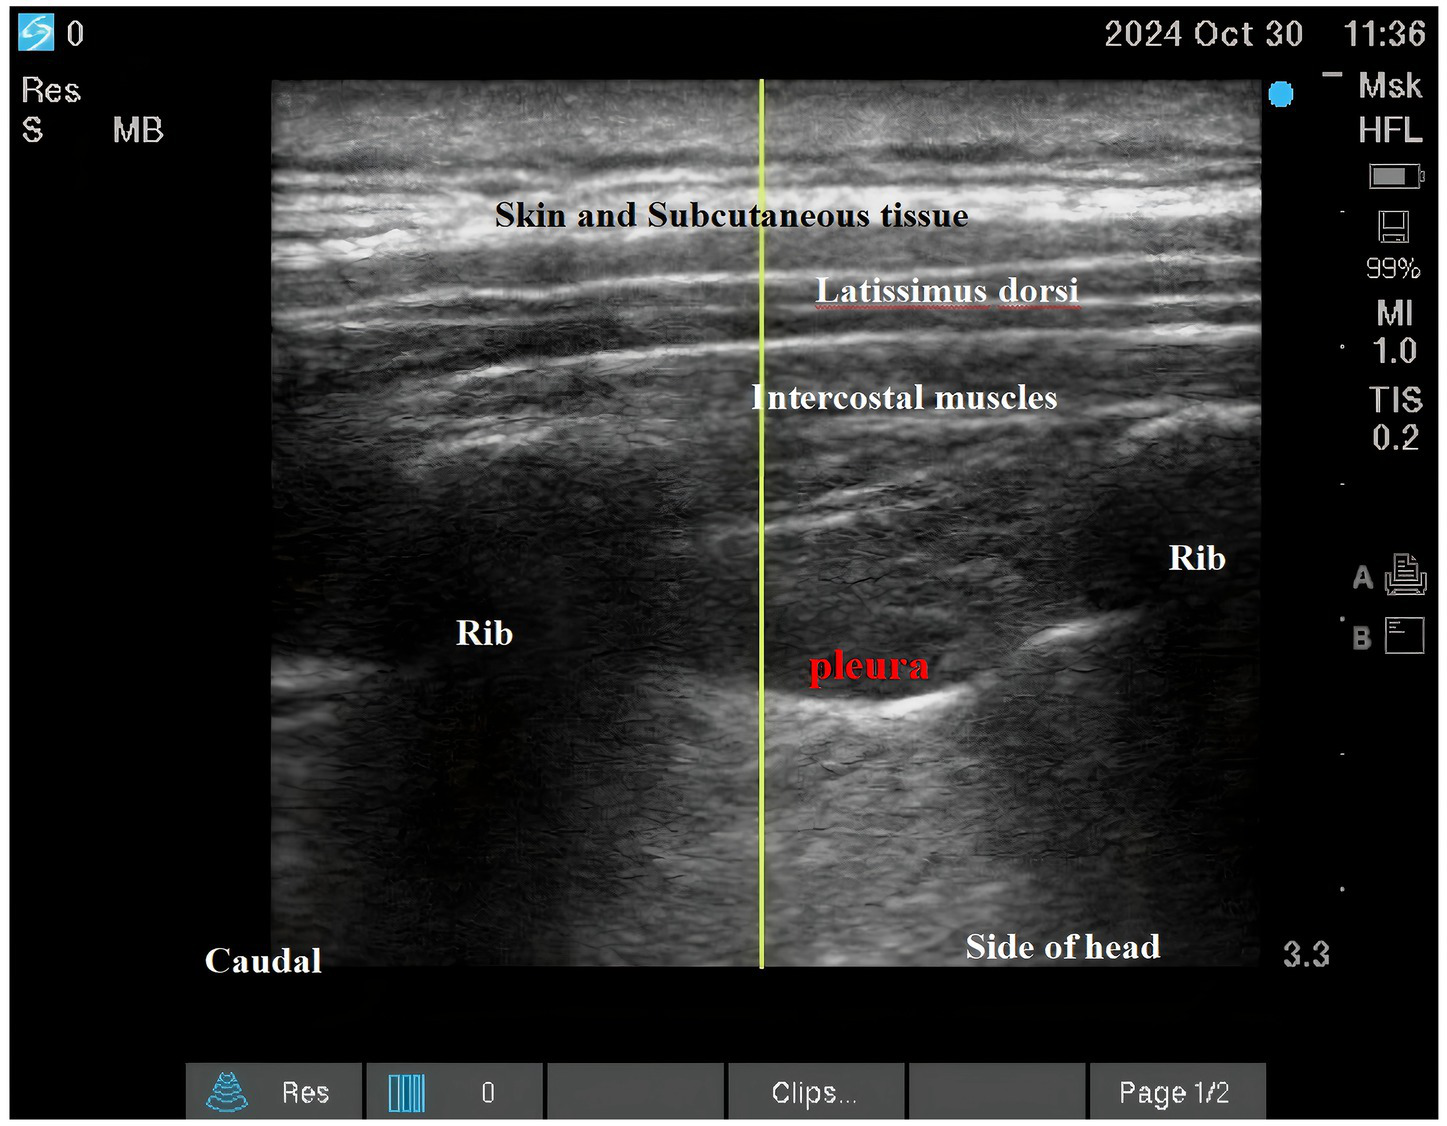

Both interventions were performed as descending intercostal nerve blocks at ribs 2–6 using a standardized ultrasound-guided technique (SonoSite X-Porte; 6–13 MHz linear transducer) by a single experienced anesthesiologist (100 prior blocks performed). Needle placement and local anesthetic spread were confirmed in both transverse and longitudinal views (See Figures 2; 3).

Figure 2

Intercostal nerve block.

Figure 3